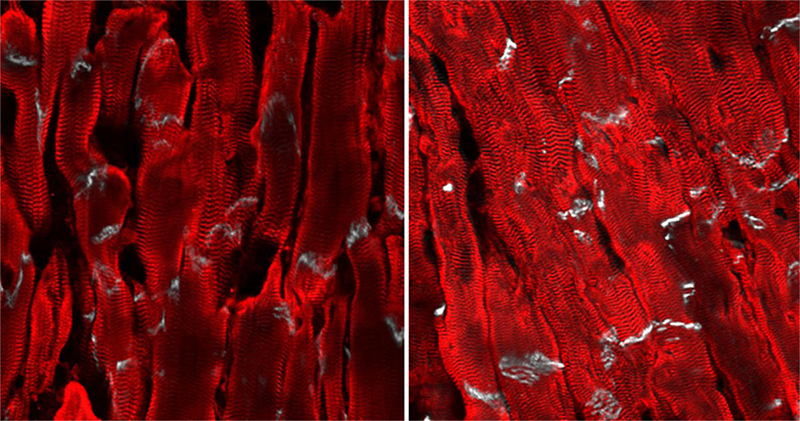

Image of mouse heart muscle

Desmoplakin knockout mouse heart muscle section (left); connexin-43 treated mouse heart muscle section (right). Image: UC San Diego Health Sciences